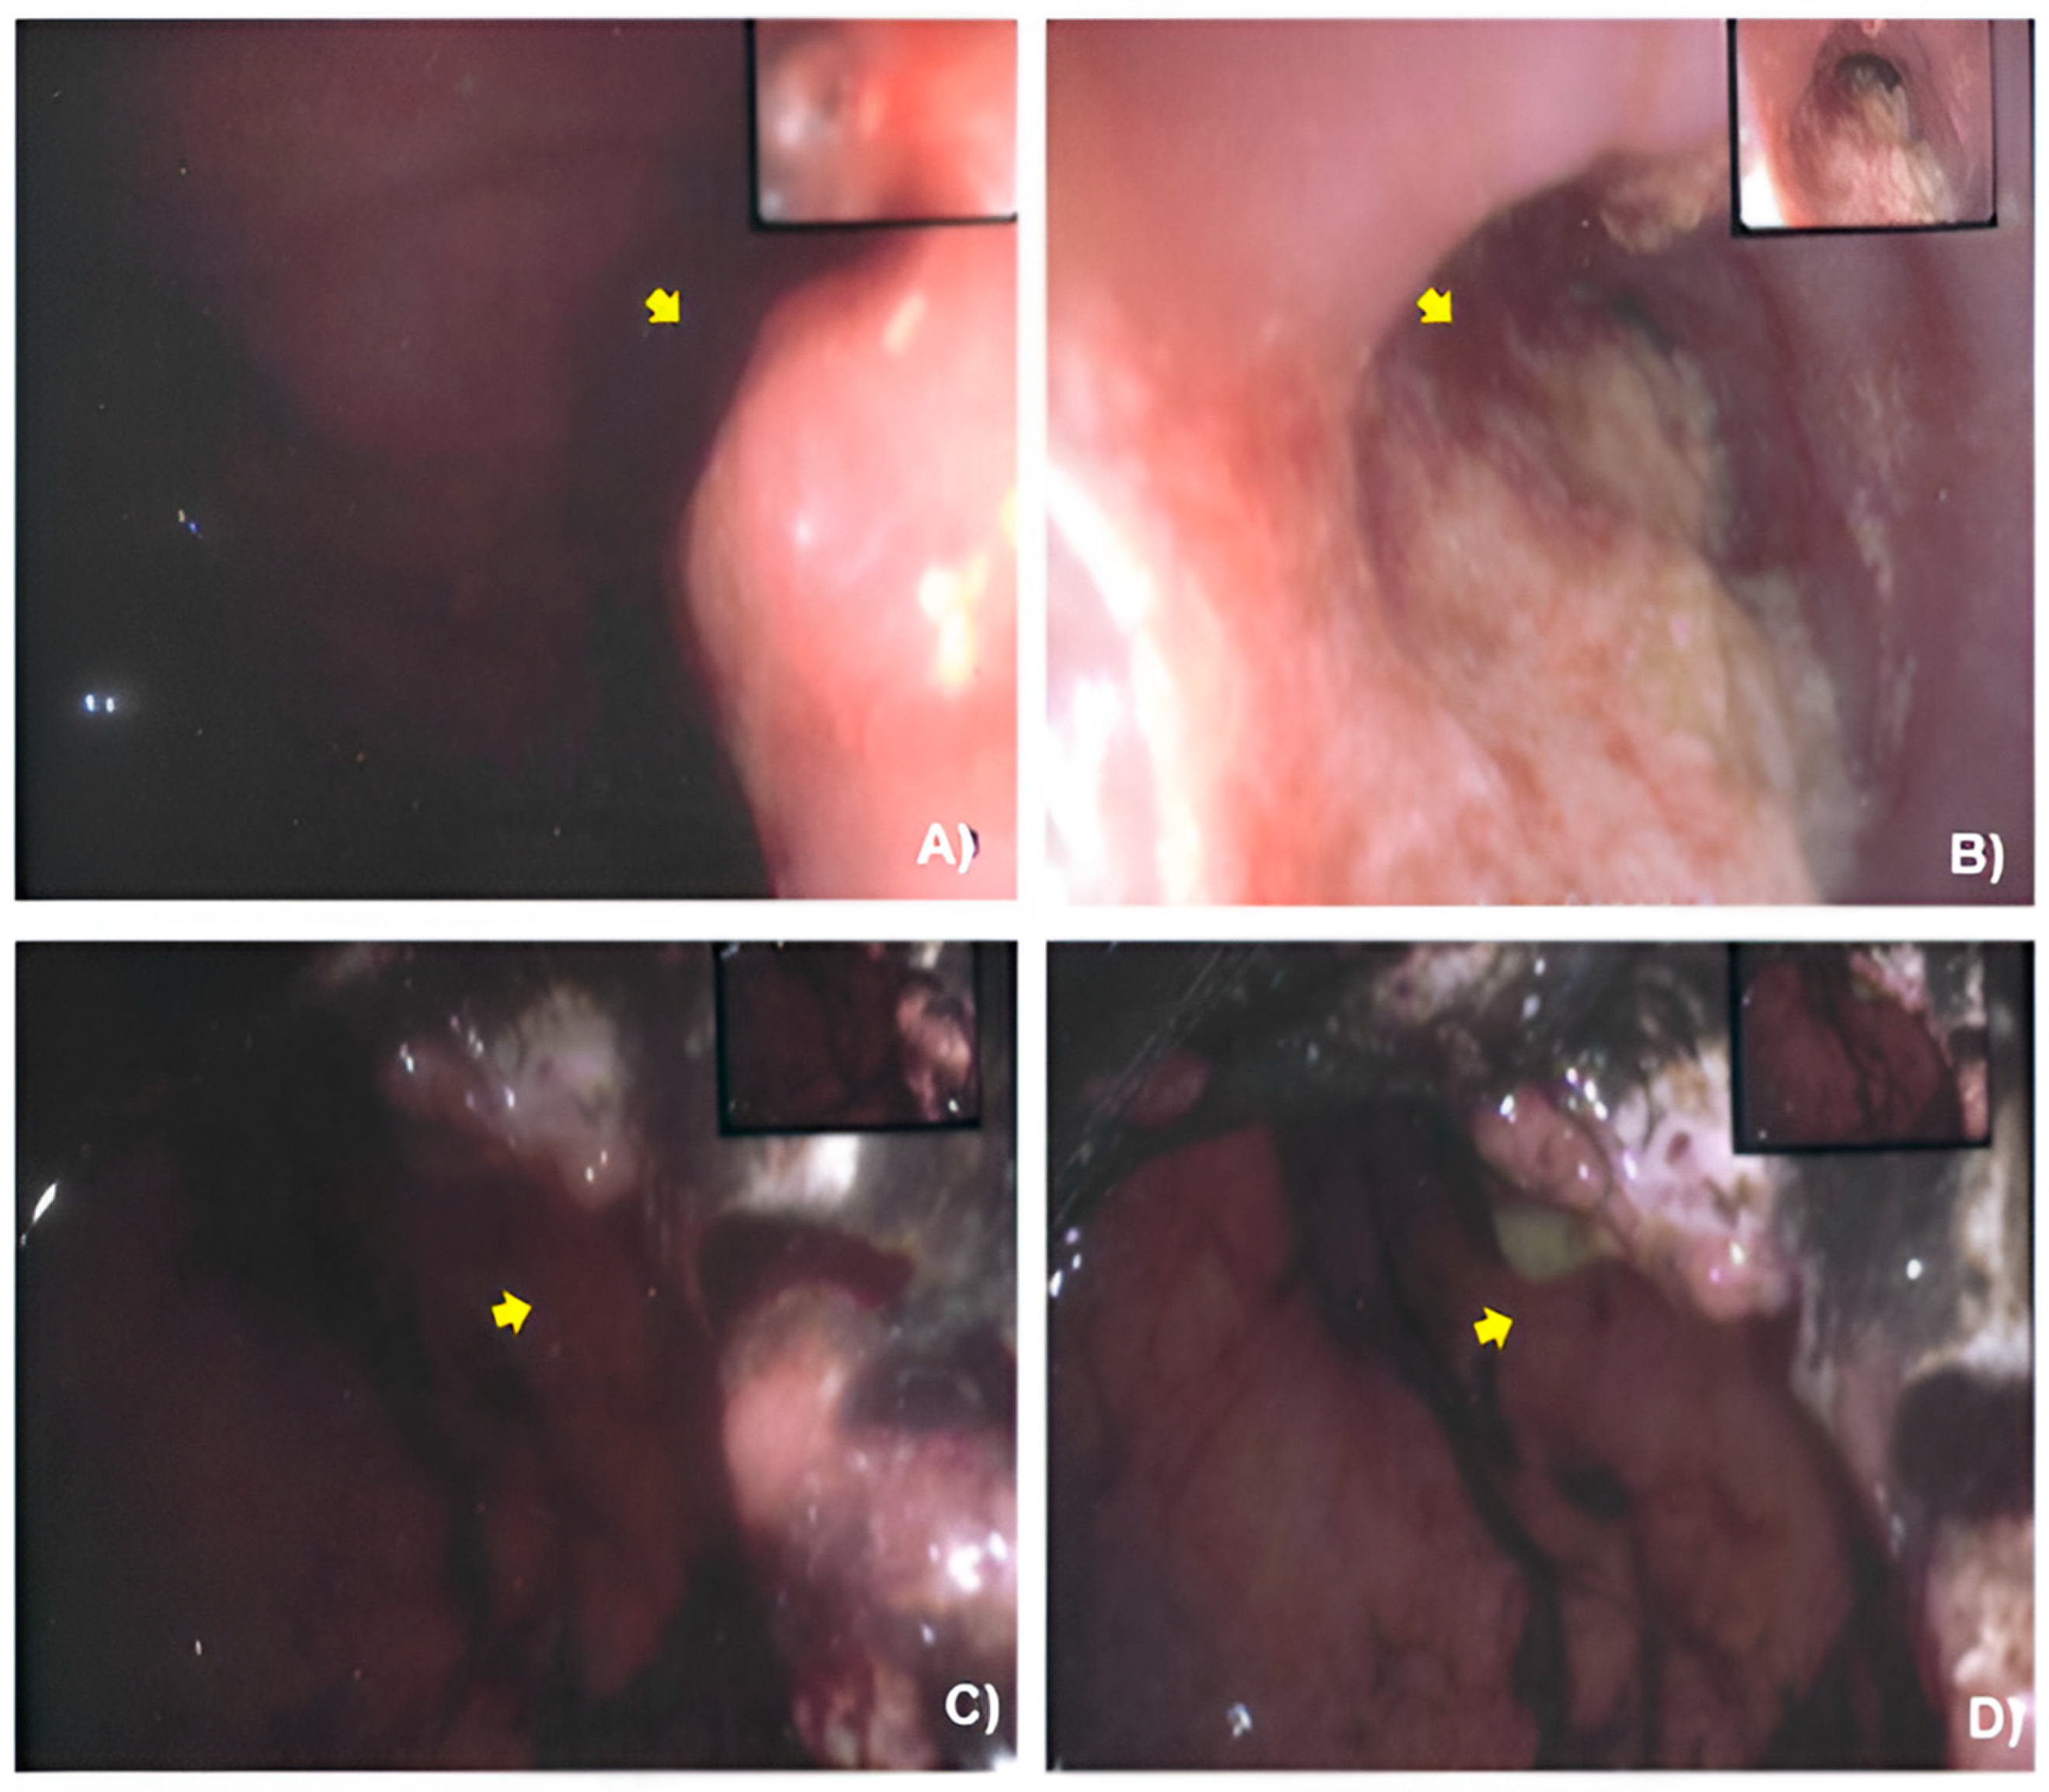

2.2. Case Presentation

3.1. Case Management